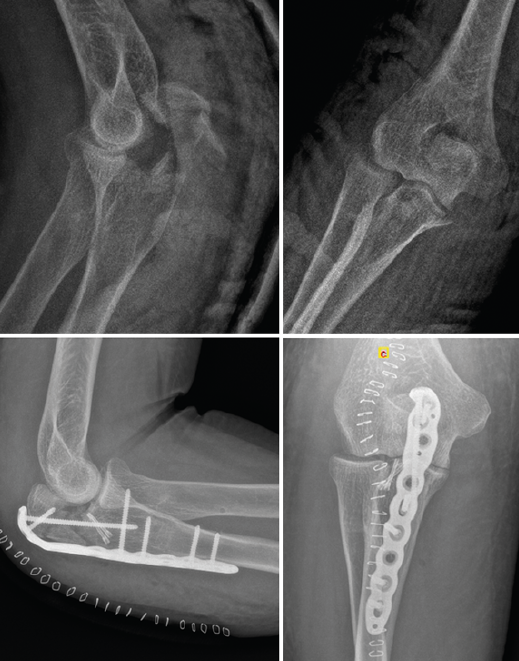

Este patrón de inestabilidad compleja de codo se caracteriza por una luxación posterior de codo asociada a 3 lesiones principales (Figura 14):

• Fractura de la cabeza del radio.

• Rotura del LCL.

• Fractura de la coronoides.

El mecanismo lesional de estas lesiones es el patrón de inestabilidad posterolateral descrito por Morrey y O’Driscoll(15).

Figura 14. Tríada terrible de codo derecho donde puede apreciarse en las imágenes de tomografía computarizada la fractura de la cabeza del radio, la fractura de la coronoides y la subluxación posterolateral de la ulnohumeral.